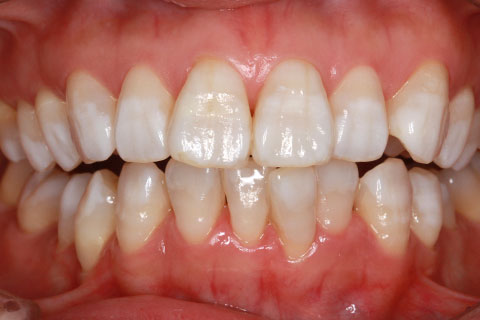

ホワイトニング

症例1

- 年齢・性別

- 23歳

- 治療期間

- 2週間

- 抜歯

- なし

- 治療費

- 4.4万円

- 備考

- ホームホワイトニング

- 治療内容

- 10~20%の漂白剤を含んだマウスピースを一日数時間装着。

- 施術の副作用(リスク)

- 一時的な知覚過敏。